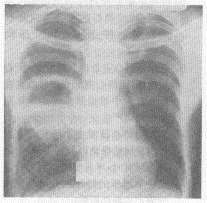

阅读胸片

正确答案:1.D;2.B;3.B;4.E;5.D 解题思路:胸片显示右肺第二、四前肋间巨大的空洞影,空洞有液平,洞壁较厚,周围有炎症浸润,是较典型的肺脓肿X线表现;结合侧位片或胸部CT还可以明确肺叶、肺段。